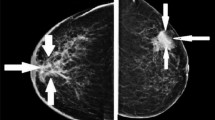

Among all the patients, we collected one cross-sectional ultrasound image of each breast tumor. All images were sourced from our Picture Archiving and Communication System and patients’ breast Static ultrasound images (JPG format) were obtained from ultrasound equipment by manufacturers including Philips and Toshiba. We removed annotations and markings from the image by minimally cropping the edges for anonymization. Then, to eliminate variations introduced by different physicians and equipment, we utilized interpolation to standardize all ultrasound images to a resolution of 960 × 720. This standardization process ensured that all images possessed a uniform resolution for subsequent analysis, thereby providing a more consistent data foundation for model training and validation. Furthermore, to improve image quality and enhance the accuracy of subsequent analysis, we processed the images using an average filter to reduce noise and artifacts within them. Experienced ultrasound physicians manually delineated the regions of interest (ROI) using ITK-SNAP (version 4.0.0, open-source software http://itksnap.org/). We implemented a comprehensive quality control protocol, which included independent sketching by multiple experts and comparison of their results, to ensure the accuracy and reliability of the sketch data.

Imaging features of the PTA, including texture, morphology, and functional information, have been proven to significantly improve the diagnostic accuracy and prognostic prediction capabilities for breast cancer21. Based on the biological characteristics of the tumor microenvironment, and considering the balance between imaging resolution and computational efficiency22, studies typically define the PTA by expanding the tumor ROI outward by 10 voxels (approximately 5–10 mm)23. Although this range selection has limitations, such as the neglect of biological heterogeneity, it can more effectively capture imaging features of the PTA compared to other voxel expansions, while avoiding the introduction of excessive background noise due to an overly large expansion. Therefore, in this study, we used Python programming to expand each patient’s tumor ROI outward by 10 voxels to form the PTA of breast tumors. Subsequently, we conducted precise segmentation of the ROI for both the tumor area (TA) and the PTA.